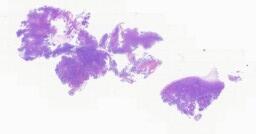

临床资料: 患者,女,38岁,右侧腰痛1月,检查发现左肾占位。入院前1月,患者无明显诱因出现右侧腰腹部疼痛,为阵发性胀痛,伴尿频、尿急、尿痛,伴有血尿,无血凝块,无恶心呕吐,无畏寒发热及其他伴随症状,期间未行特殊处理。20+天前于我院就诊,完善监测提示“右输尿管结石;左肾下极占位:性质待定”。CT:左肾下份见团块状等、稍低混杂密度影,大小约3.5cm×3.0cm,增强扫描可见不均匀强化,边界较清。右侧输尿管壁内段结石,其上方输尿管、肾盂肾盏积水扩张伴感染。术中见:左肾下极占位约4×3cm,突出于肾脏表面,周围稍粘连。

大体所见: 巨检:“左肾部分”:已剖部分肾组织一块,大小5×3.5×3cm,临床切开处见一肿物,大小3×3×2.5cm,肿物周围肾组织呈囊性,囊内壁灰白厚约0.1-0.2cm,肿物较破碎,呈灰黄色,部分附着于囊内,另见游离破碎肿瘤组织大小共约5×3×1cm,切面均灰黄实性质中。

免疫组化: 无